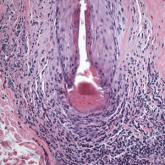

ArticleHair Follicle Bulb Region: A Potential Nidus for the Formation of Osteoma CutisAuthor:Arif Suhail Usmani, MDPublish date: February 3, 2021Understanding the pathogenesis of osteoma cutis can help physicians devise management of these disfiguring lesions.Read More